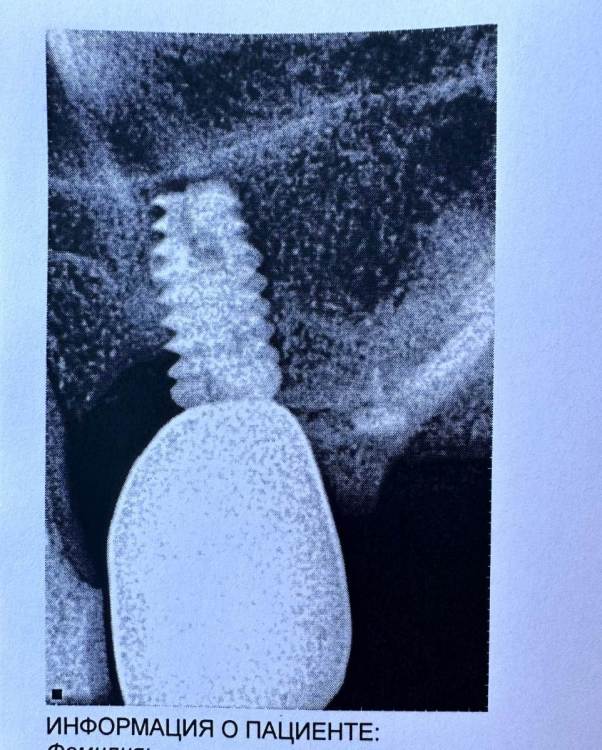

Mitt Опубликовано 29 октября, 2023 Поделиться Опубликовано 29 октября, 2023 (изменено) Здравствуйте. Ж., 39 лет. Так получилось, что мне нужно решить, что делать с имплантатом на месте верхней шестерки. А тк я не обладаю необходимой компетенцией, очень нуждаюсь в подсказках специалистов. Дано: 1. 2014-2015 гг - удаление зуба, синус лифтинг, имплантация с пластикой мягких тканей, установка коронки. 2. 2015 - 2019 гг - проблема контактов с рядом находящимися пятым и седьмым зубами, воспаление десны вокруг 5, имплантант, 7. Решалось путем композитных «накладок» на 5 и 7 зубы. 3. 2019 - 2023 гг - пластика мягких тканей, удаление 7 зуба с подсыпкой графта, еще штуки 3 или 4 пластики, включая вестибулопластику, временная коронка. 4. 2023 г - установка новой постоянной коронки, 5 месяцев тишины, с августа гной в районе имплантата (десна спокойна). Проблемы общие для всех временных периодов - тандем с пазухой и периодические ближе к постоянным боли разной интенсивности и локации (пазуха, 7 зуб, место от 7 зуба, стенка носа, кость), мне сложно лоцировать( Мне нужно выбрать, что делать дальше: попробовать почистить имплантат, или уже отпустить=удалить. Вариант почистить и еще сделать пластику пока не рассматриваю, тк после стольких пластик частичная парастезия неба. Может быть, кто-то подскажет, к какому решению в итоге прийти.. P.s. Я не знаю , какие скрины кт нужны( кт 08.2023 Изменено 29 октября, 2023 пользователем Mitt Ссылка на комментарий